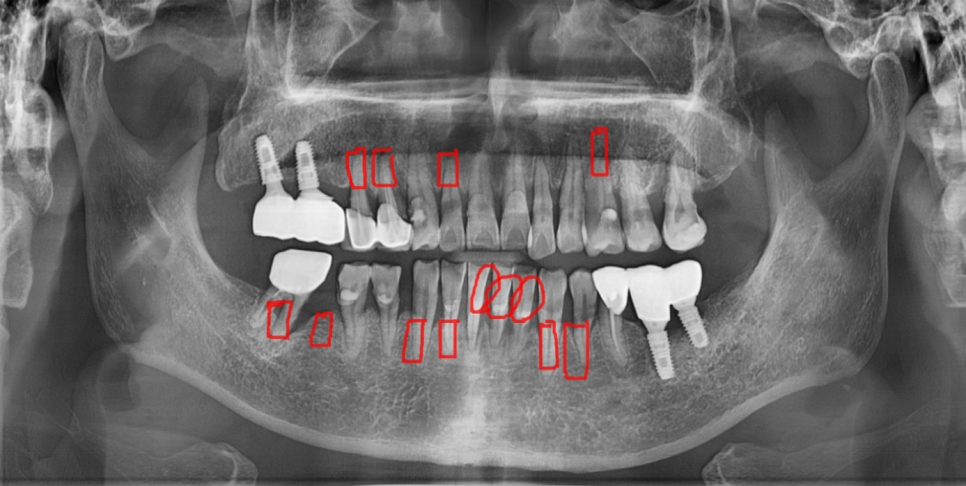

검사를 위해 찍어본 x ray

전형적인 풍치 증상입니다.

녹아버린 잇몸뼈로 치아가 흔들 흔들

길어 보이는 상황이었습니다.

양치도 전반적으로 안되어있어

치태라고 하는 찌꺼기들이 치아 전반적으로 붙어있었습니다.

구강위생이 불량하니 잇몸이 더 빨리 무너졌네요~~

기타 증상으로는 녹아버린 잇몸뼈로

잇몸이 위로 올라가다보니 치아 뿌리 부분이 노출

양치가 안되면서 뿌리부분이 썩고,

전반적으로 파여있는 모습이었습니다.